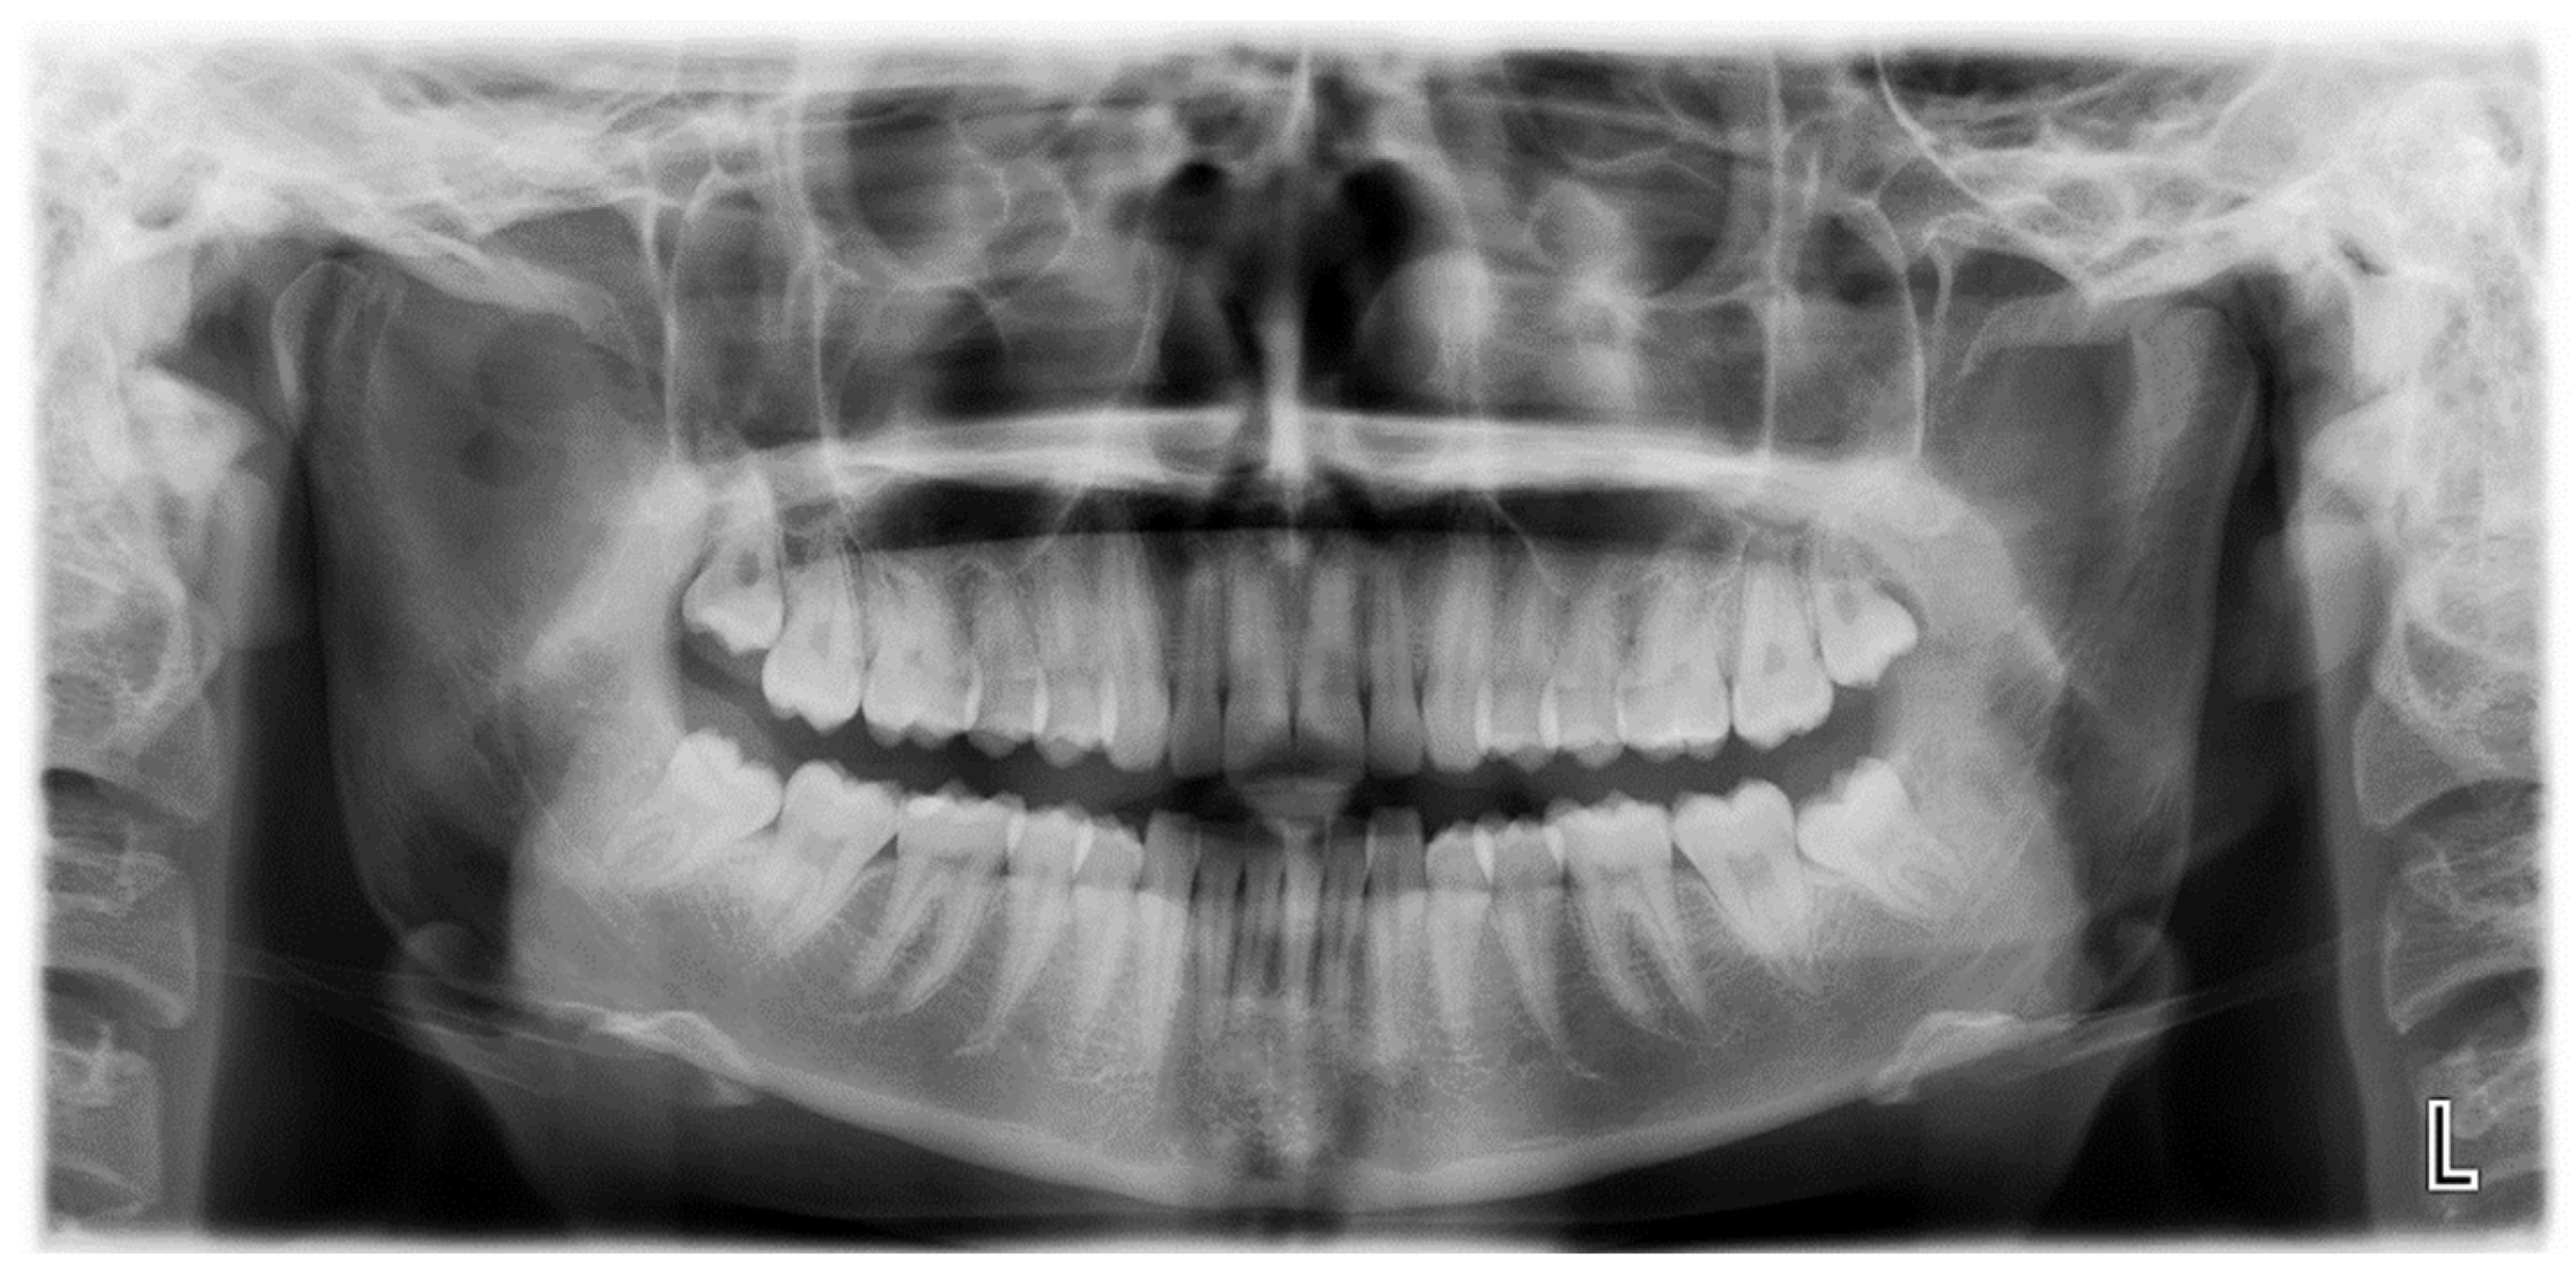

| 114 | Raccampo et al. | 2022 | 19 | F | R | CCE | 25 | 40 | Intraoral coronoidectomy | 12 | No |

| 115 | Raccampo et al. | 2022 | 18 | M | R | OC | 20 | 44 | Intraoral coronoidectomy | 12 | No |

| 116 | Raccampo et al. | 2022 | 23 | M | R/L | CH | 20 | 37 | Intraoral coronoidectomy | 14 | No |